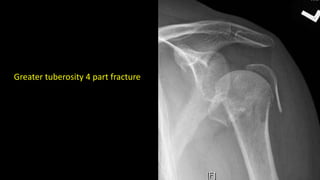

Greater tuberosity 4 part fracture

Greater tuberosity 4part fracture